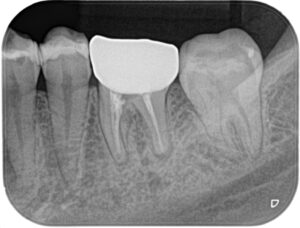

Before/After X線写真

(画像:xray_rc1.jpg 治療前後のX線比較)

治療前は根尖部に明確な透過像(感染像)が認められましたが、治療後は封鎖が確認でき、感染範囲も改善傾向にあります。